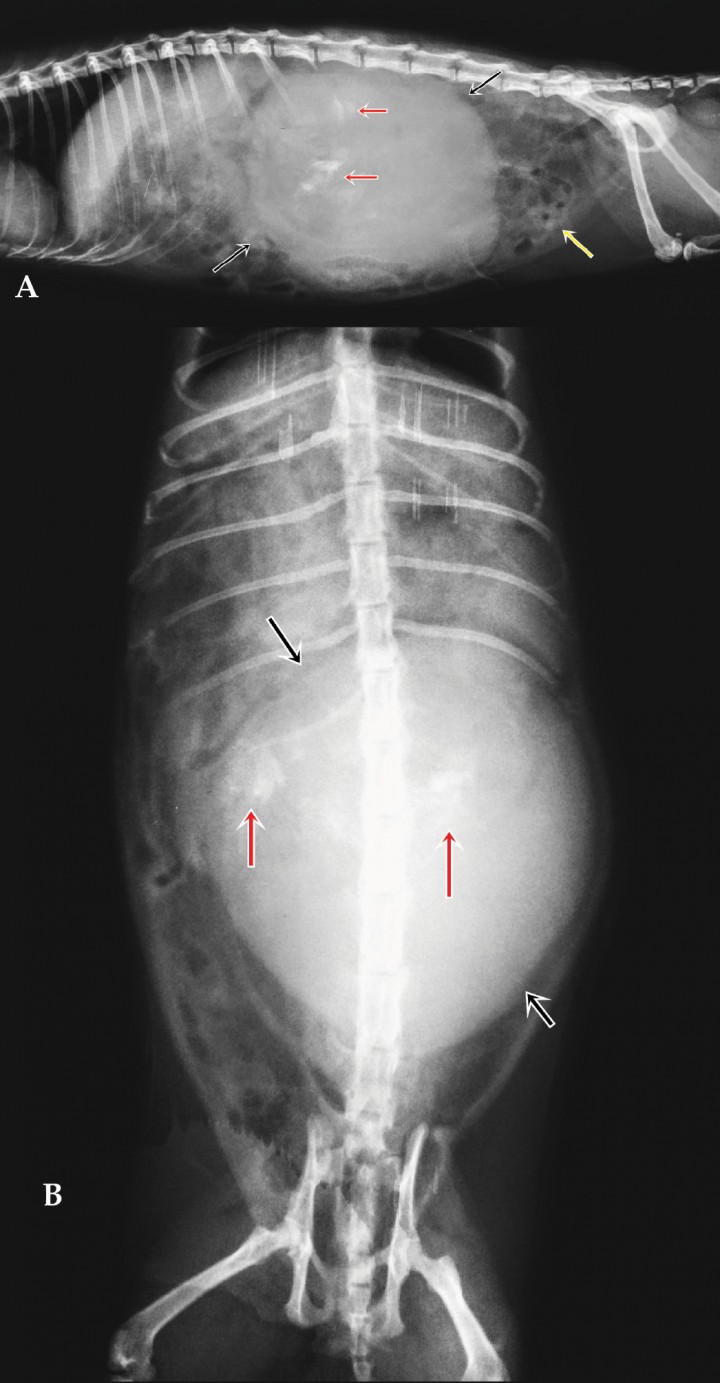

Se procedió a la realización de un estudio ecográfico abdominal. Se observó la presencia de una masa de 4,2 x 6,1 cm de estructura heterogénea y un patrón de ecogenicidad mixto, rodeada por una cápsula, que envolvía el riñón izquierdo (Fig. 2). Este último se encontraba comprimido por la masa, aunque presentaba una estructura aparentemente normal salvo por la presencia de leve edema subcapsular. La zona craneal de la masa mostraba un parénquima hipoecoico sugestivo de contener líquido, dividido en varios compartimentos (Fig. 2C). Aunque el tamaño de la masa dificultaba el examen ecográfico, no se observaron alteraciones en el resto del abdomen.

<p>Imágenes de ecografía abdominal. (A) Se observa una masa de ecotextura heterogénea, bordes irregulares, sin aparente órgano-dependencia. Muestra zonas hiperecogénicas (flecha roja) de distribución aleatoria por el parénquima. Se aprecian, además, zonas hipoecoicas compatibles con contenido líquido (flechas amarillas). (B) Se aprecia el riñón izquierdo comprimido por la masa, y rodeado por la cápsula de la misma. Se puede observar edema subcapsular del riñón. (C) La zona craneal de la masa muestra un parénquima hipoecoico heterogéneo, sugestivo de consistencia líquida (zona superior), dividido en compartimentos por posible tejido fibroso. Se observan zonas que proyectan sombra acústica (flechas rojas) compatibles con calcificaciones.</p>

Imágenes de ecografía abdominal. (A) Se observa una masa de ecotextura heterogénea, bordes irregulares, sin aparente órgano-dependencia. Muestra zonas hiperecogénicas (flecha roja) de distribución aleatoria por el parénquima. Se aprecian, además, zonas hipoecoicas compatibles con contenido líquido (flechas amarillas). (B) Se aprecia el riñón izquierdo comprimido por la masa, y rodeado por la cápsula de la misma. Se puede observar edema subcapsular del riñón. (C) La zona craneal de la masa muestra un parénquima hipoecoico heterogéneo, sugestivo de consistencia líquida (zona superior), dividido en compartimentos por posible tejido fibroso. Se observan zonas que proyectan sombra acústica (flechas rojas) compatibles con calcificaciones.